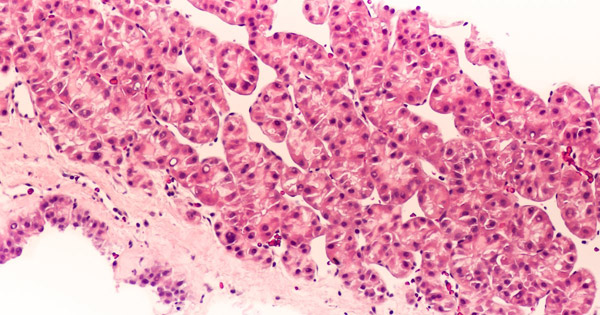

約80%的肝癌患者都有乙肝及肝硬化的背景。全球每年與乙肝病毒感染相關(guān)的肝細(xì)胞癌(HCC)患者有超42萬(wàn)例。

LioCyx-M004是一種從T細(xì)胞中提取的轉(zhuǎn)基因自體細(xì)胞療法,該T細(xì)胞經(jīng)mRNA編碼后表達(dá)T細(xì)胞受體(TCR),該受體能夠識(shí)別肝癌細(xì)胞表面的乙肝表面抗原。